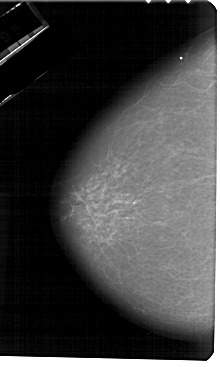

A_1267_1.LEFT_CC

LEFT_CC LINES 5491 PIXELS_PER_LINE 3286 BITS_PER_PIXEL 12 RESOLUTION 43.5 NON_OVERLAY